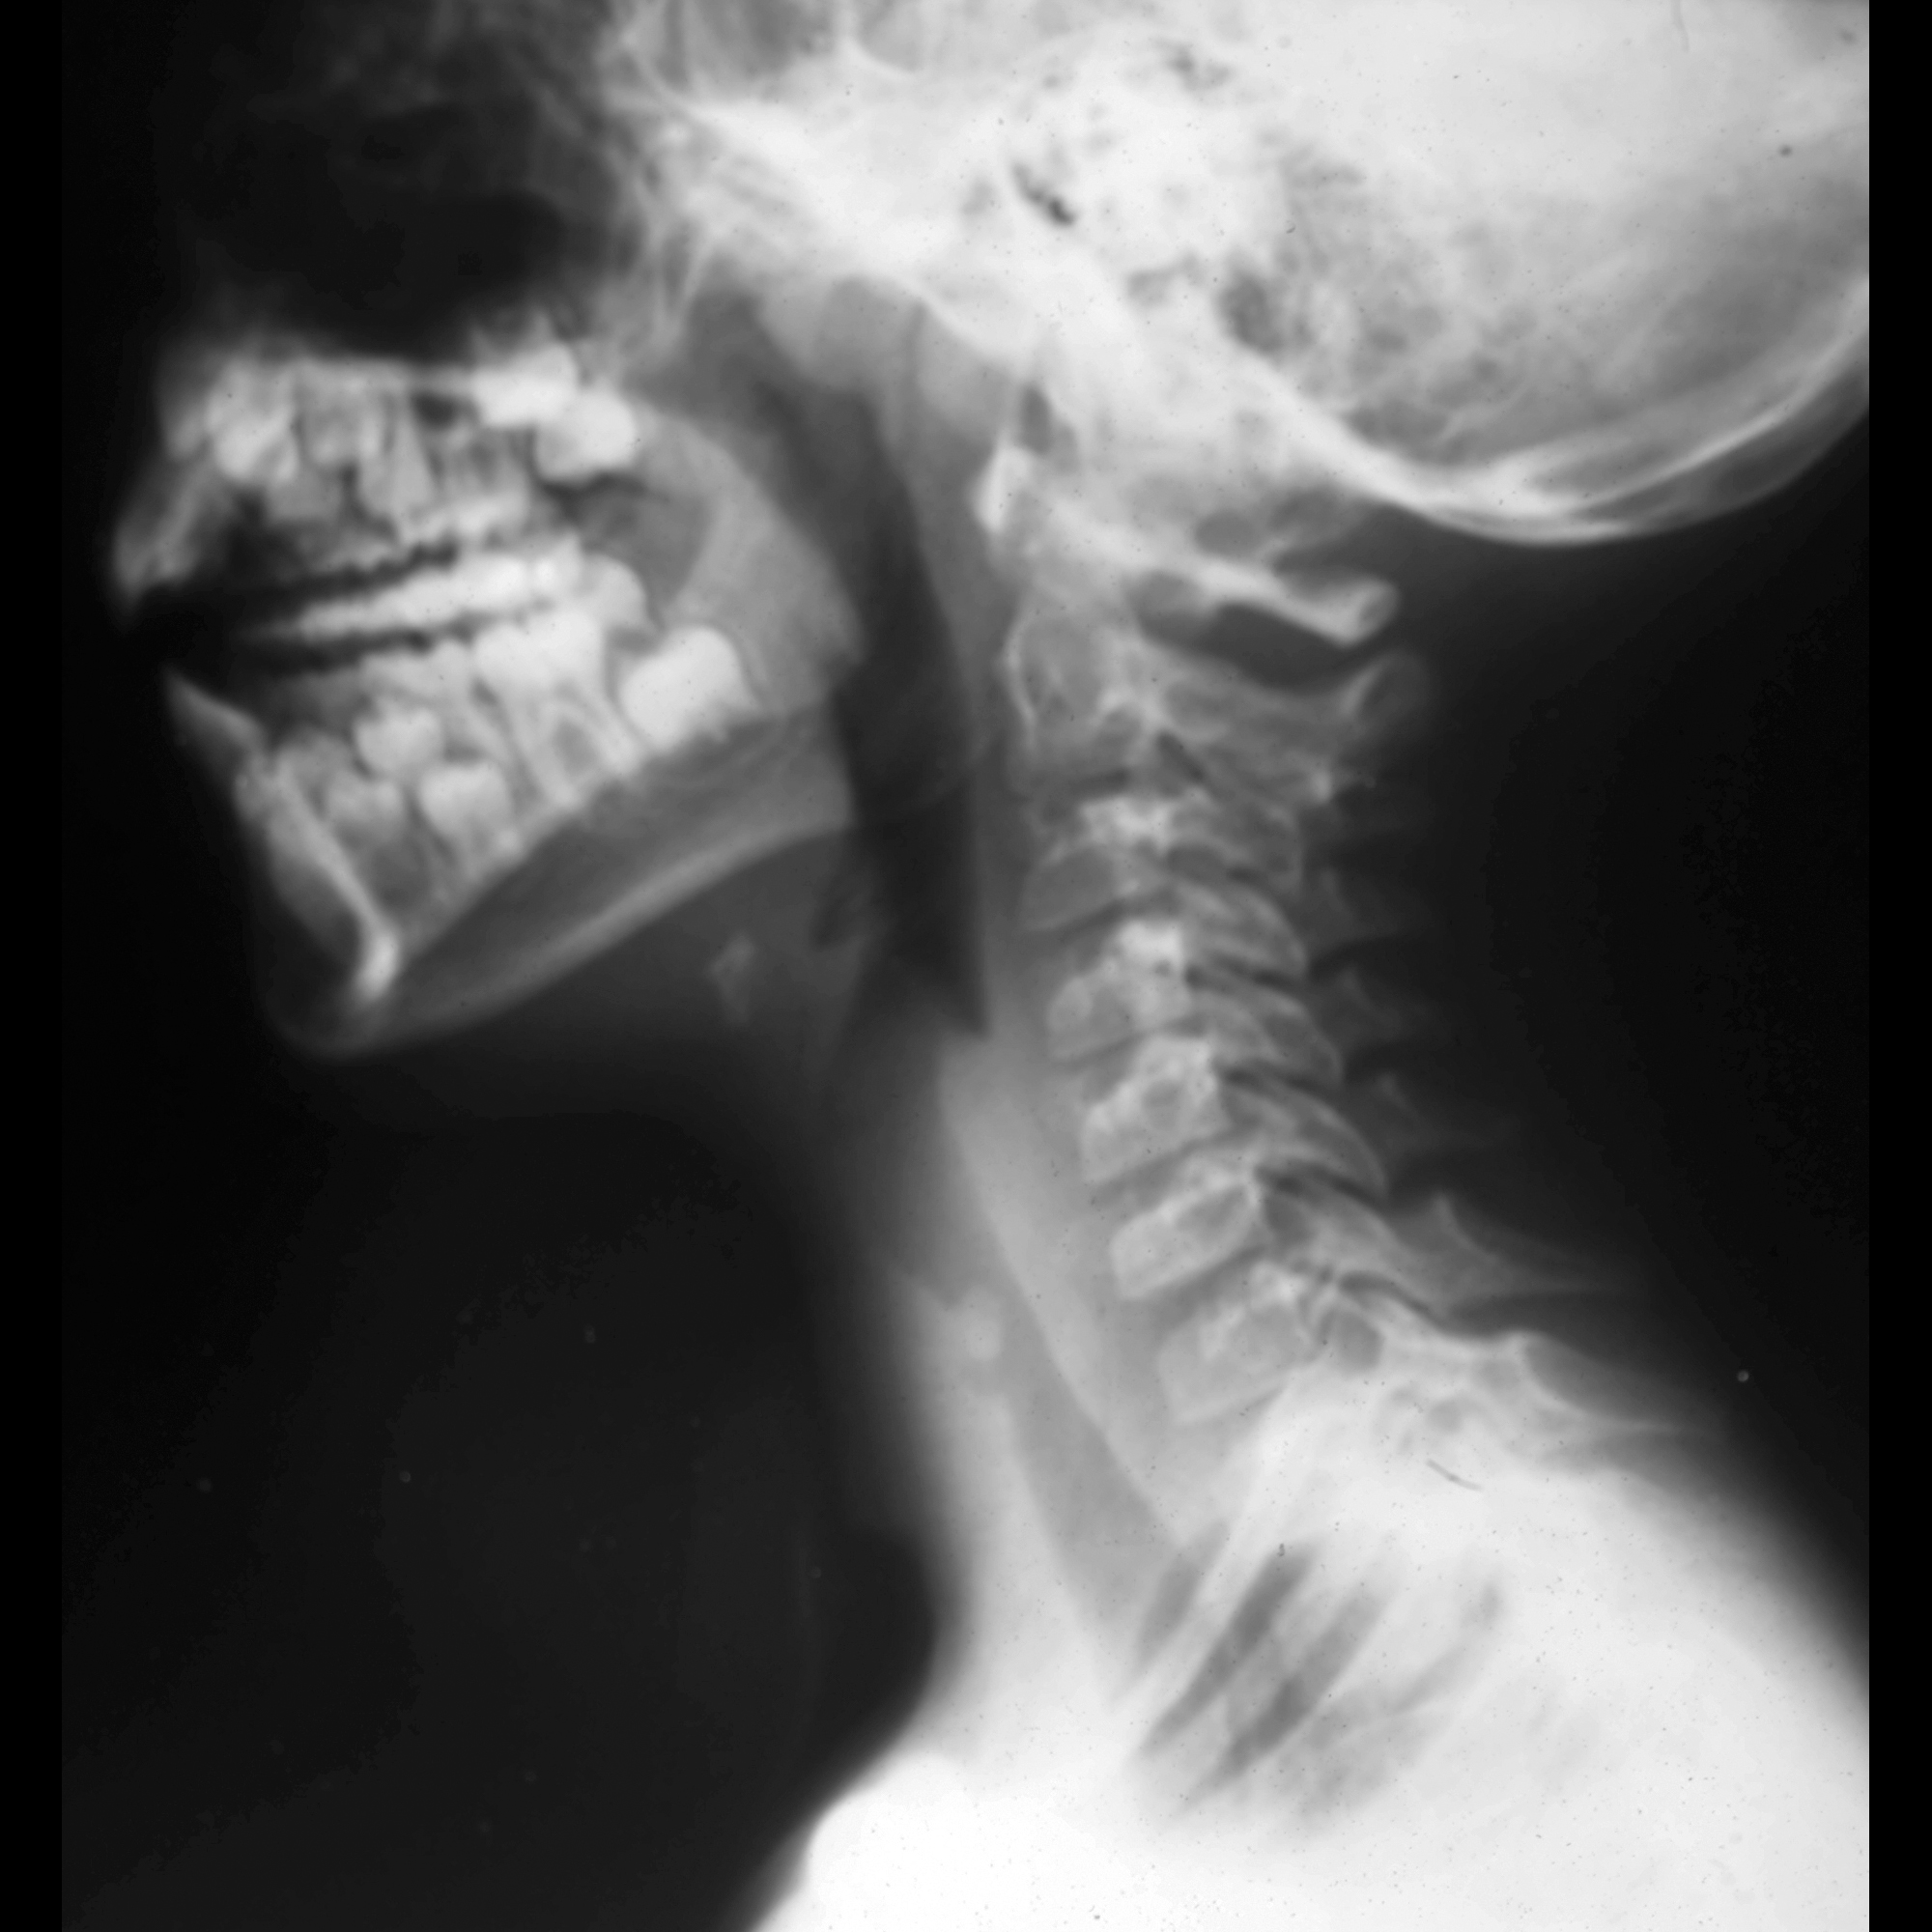

PPT Laryngeal complications of endotracheal intubation PowerPoint Presentation ID211103 History Of Endotracheal Intubation endotracheal intubation came into routine use after the introduction of muscle relaxants into anesthesia practice. [1] in its simplest form, it is a. Unfortunately, this procedure also carries a high risk of. the endotracheal tube (ett) was first reliably used in the early 1900s. history and early development of the endotracheal tube. To present a concise history. History Of Endotracheal Intubation.

PPT Laryngeal complications of endotracheal intubation PowerPoint Presentation ID211103 History Of Endotracheal Intubation tracheal intubation is commonly performed in critically ill patients. endotracheal intubation came into routine use after the introduction of muscle relaxants into anesthesia practice. modern endotracheal tubes, airway protective devices, which promote safe passage of a wide array of gases in both. the endotracheal tube (ett) was first reliably used in the early 1900s. To present. History Of Endotracheal Intubation.